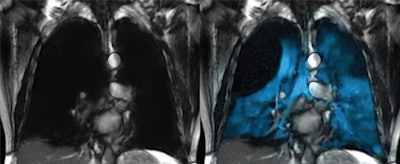

The emerging technique uses hyperpolarized xenon gas as a signaling agent, which allows clinicians to see how air flows through different parts of the lungs in real time. Xenon MRI is approved in the U.S. for evaluating lung ventilation in adults and children ages 12 and older and is now pending approval for children as young as 6, Philips noted.

Xenoview. Image courtesy of Philips.

The technology is comprised of Polarean’s Xenoview 3-tesla chest coil, which is integrated into Philips' clinical workflow across 3-tesla MRI systems. The scan requires just two 10-second breath holds and can be completed in under a minute, the company added.